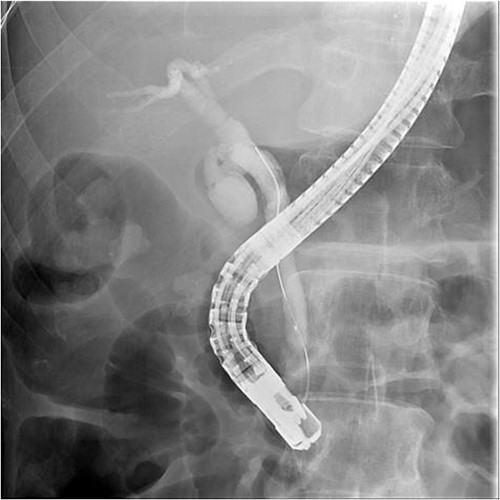

And then, a 7 French bostone scientific plastic stent was inserted over the guide wire for bile diversion. However, hemobilia was noted to be draining out from the stent right after. After reviewing the image, we realised that PVC was probably made (Fig. 3). After discussing with the general surgeon, we decided to arrange immediate surgical exploration to check for collateral damage and remove the CBD stones for cholangitis resolution. The stent was thus left inside for surgical guidance. Before the surgery, abdomen computed tomography (CT) was done and revealed retained contrast medium in the bile duct (Fig. 4) and malposition of the CBD internal stent with upper portion in the main portal vein (Fig. 5).

Fluoroscopy image showed the plastic stent penetrated through the CBD.